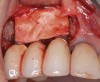

(6.) A 3.6-mm diameter implant was removed with a 4.0-mm diameter trephine drill. The apical portion of the implant was luxated carefully to preserve as much bone as possible.

Figure 6

(7.) Because apical and lateral bone volume was preserved with use of an ultrathin trephine, a wider diameter, 4.2-mm implant was placed at the time of implant removal. Bone augmentation was performed, and submerged healing was selected.

Figure 7